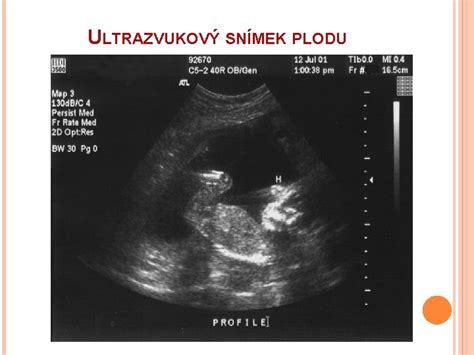

V priebehu 8. týždňa tehotenstva plod rastie zo dňa na deň a CRL (temenokostrčná dĺžka) parameter môže byť od 16 do 20 mm. Veľkosť plodu by sa dala prirovnať k zrnku kávy, fazuľke alebo maline. Napriek tomu dokáže ultrazvuk vidieť kontúry, teraz už malého človiečika. V ústach sa dokonca nachádza malý jazyk a viditeľné sú aj pery. V oku sa tvorí sietnica ale ešte ich prekrývajú rastúce viečka. Pri ultrasonografickom vyšetrení už môže byť vidno tvar tela, plecia, lakte či kolená. Chvostík už takmer zmizol. Aktivita embrya sa prejavuje spontánnymi pohybmi. Práve v tomto období sa väčšina žien dočká termínu tehotenskej poradne. Pôjde teda o prvé vstupné vyšetrenie, ktorým sa môže definitívne potvrdiť klinické tehotenstvo. V 8. týždni tehotenstva by už mal ultrazvuk potvrdiť prítomnosť plodového vaku i embrya. Lekár stále môže využívať transvaginálnu sondu, ktorú zavedie do pošvy a identifikuje obsah maternice. Pri ultrazvuku môže premerať CRL plodu, čo slúži na zistenie štádia tehotenstva. Tým, že prídete nalačno, realizuje sa odber krvi a robí sa kompletný krvný obraz aj so zisťovaním krvnej skupiny a RH faktora. Zisťujú sa protilátky v krvi na rôzne ochorenia, kontroluje sa obsah bielkovín v moči (pozn. pre prípad vzniku preeklampsie). Lekár sa zaujíma o vašu rodinnú anamnézu, alergie, dedičné ochorenia, lieky, ktoré beriete a celkový zdravotný stav. Informujte ho o príznakoch, ktoré pociťujete. Takisto si vás lekár odváži a premeria. Viesť si budete tehotenskú knižku. Odporučiť môže lekár prípadne ďalšie vyšetrenia u potrebných špecialistov.